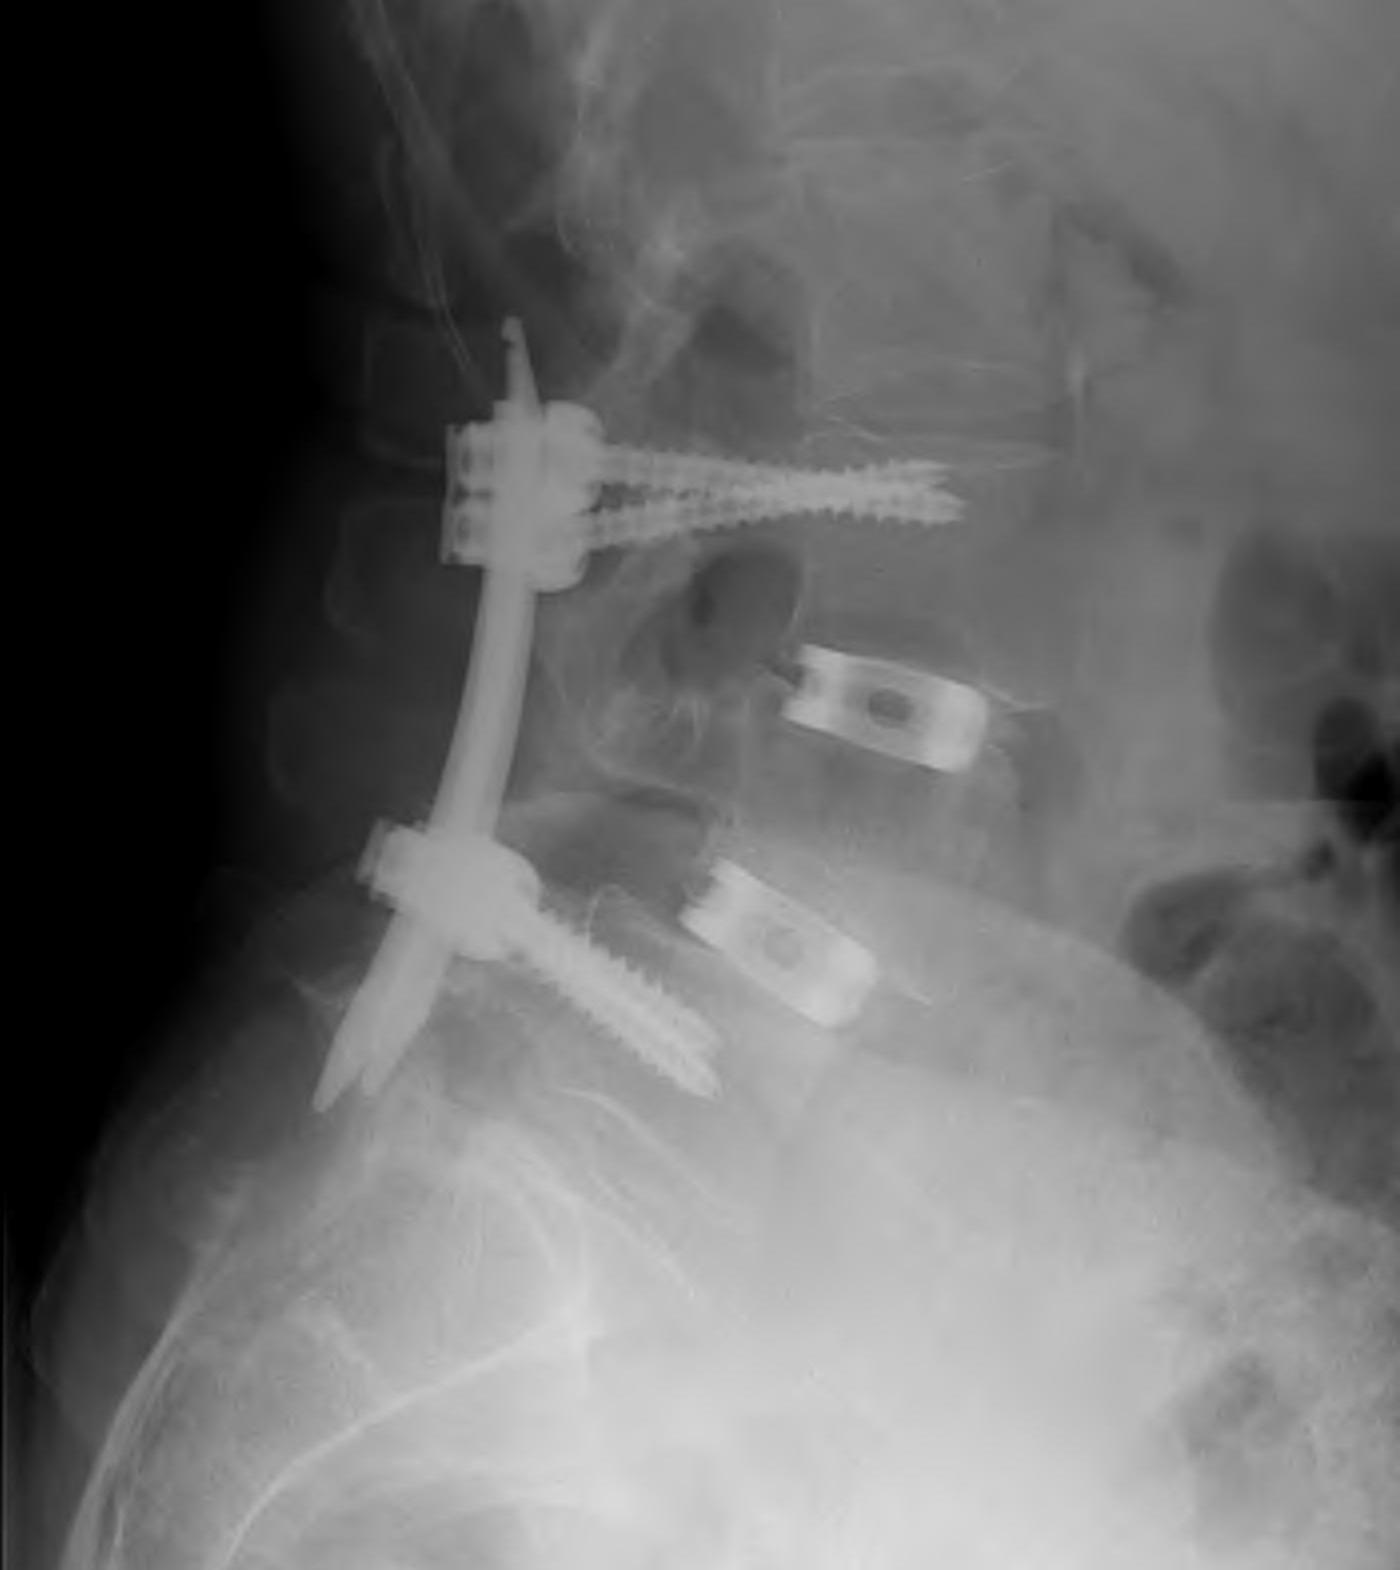

Decompression + Instrumented Posterolateral Fusion

Technique

Midline incision

- elevate para-spinal muscles

- expose L4/5 facets and TP's

- laminectomy +/- foraminotomy

- pedicle screws + rods

- decorticate lamina, transverse processes, facet joints

- posterolateral fusion with BMP collagen and synthetic BG sushi rolls